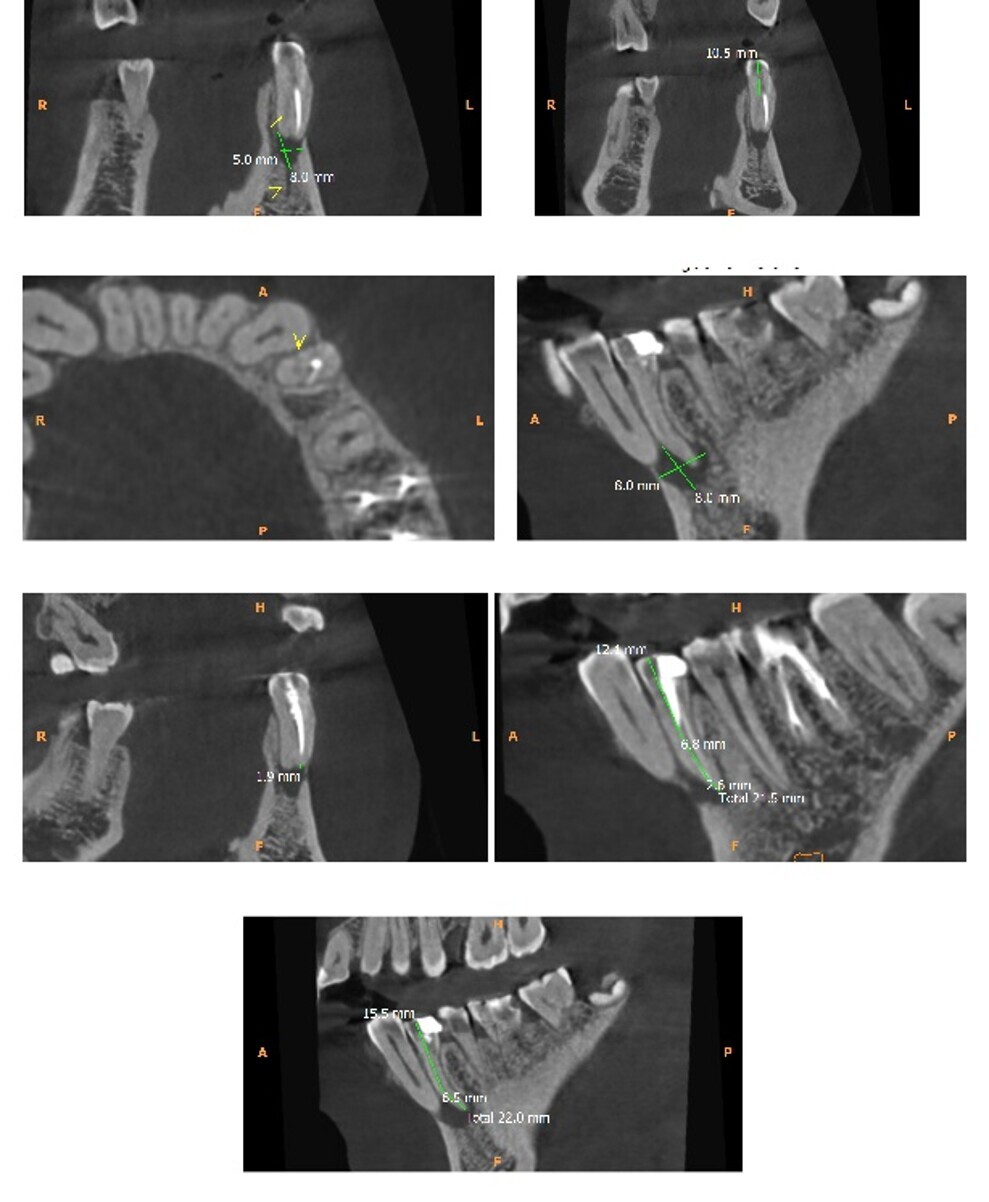

Fig 3. Scan sections

The patient was sent for 3-D imaging (CBCT) for more details and a precise diagnosis.

The CBCT imaging revealed the following findings with tooth 34

A partially endodontic treated 34.

Single root with the canal bifurcating about 10.5mm below the crown to form buccal and lingual canals.

Buccal canal filling short of apex.

Missed lingual canal space noted. A suspected perforation involving the mesial dentinal wall along the mid-canal region (near the bifurcation).

Large periapical lesion measuring 8.0 x 8.0 x 5.0mm perforating buccal plate along with mild external root end resorption. (Figure 3)